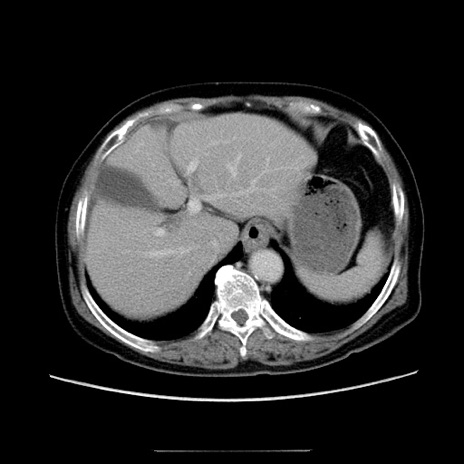

症例5(横断像)

【症例】70歳代女性

【主訴】お腹が張る

【現病歴】1週間くらい前から腹部膨満の自覚あり。昨日夜から増悪したため、本日救急外来受診。

【身体所見】意識清明、BT 36.5℃、BP 165/106mmHg、HR 80bpm、SpO2 98%、腹部:膨満、軟、自発痛・圧痛なし、触診にて不快感あり、腸蠕動音:減弱

【データ】WBC 12600、CRP 1.04